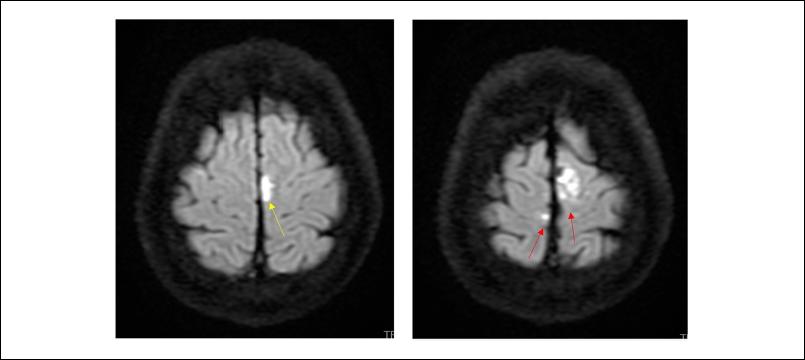

De la valoración neurológica se destaca: electroencefalograma (EEG) al ingreso sin actividad epileptógena, resonancia nuclear magnética (RNM) signos de meningitis a nivel frontal parasagital bilateral (Figuras 1 y 2), cerebritis a nivel de hemisferio cerebeloso izquierdo, sin otras complicaciones. Se otorga alta de terapia intensiva a los 7 días con buena evolución y sin secuelas.